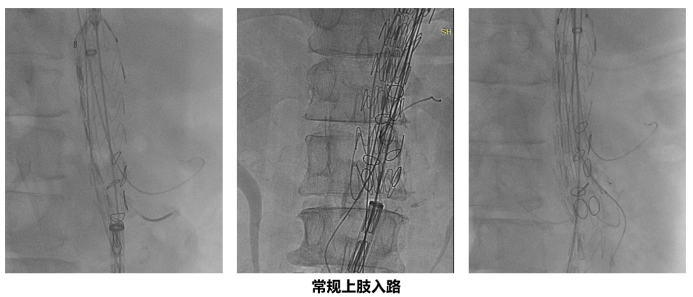

上肢入路:经典背后的隐忧

长期以来,上肢入路是进行内脏四分支重建的常规选择。通过双侧腋动脉切开,置入大口径鞘管,为导丝、导管及支架输送系统提供通路。这种方法路径直接,对于初学者而言,逐一分支超选的成功率相对较高。

然而,随着临床实践的深入,其弊端也愈发明显:

神经系统风险高:鞘管及器械通过主动脉弓时,极易扰动弓部及弓上血管起始处的易损斑块,导致脑栓塞;同时,大口径鞘管可能部分阻塞颈动脉或椎动脉开口,造成远端低灌注。数据显示,上肢入路的围术期脑血管事件发生率(2.8%)显著高于下肢入路(1.2%)。

创伤与失血量大:上肢动脉切开本身即为有创操作,且术中因鞘管密封问题常伴有持续性渗血,复杂手术耗时数小时,累积失血量可达1000ml,增加患者负担。

解剖限制多:对于III型主动脉弓、降主动脉极度扭曲、既往有弓部重建史、弓部存在大量附壁血栓或上肢动脉本身闭塞的患者,上肢入路往往难以实施甚至成为禁忌。

操作体验差:手术时间长,术者需长时间暴露于X线下(“吃线多”),操作舒适度和效率均受影响。